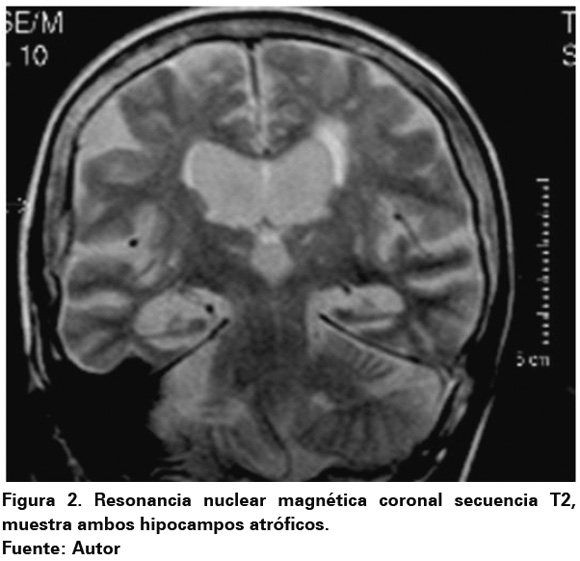

La atrofia a nivel hipocámpico se observa prácticamente en todos los pacientes con EA29 así como en muchos individuos que cursan con demencia de origen vascular30. Últimamente se ha prestado más atención a los cambios en el hipocampo en pacientes con depresión, así lo demuestran varios estudios de Resonancia Magnética Nuclear (RMN) que han documentado la presencia de hipocampos más pequeños en sujetos con depresión31,32 (Ver Figura 2). Además de los factores previamente mencionados, la región CA1 hipocampal y el subículo son particularmente vulnerables al envejecimiento y a cambios relacionados con el mismo33.

Dichas modificaciones generan un estado de hipercortisolemia prolongada capaz de generar atrofia del hipocampo, esta interacción puede explicar la asociación observada entre estados de hipercortisolemia como el síndrome de Cushing y la depresión.